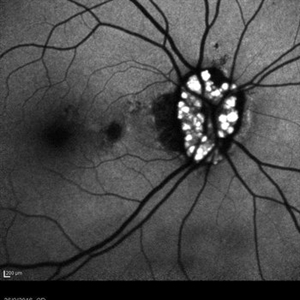

Retinal Astrocytoma

Retinal astrocytoma, also known as astrocytic hamartoma, is a rare benign tumor that occurs in the retina of the eye. It is a type of hamartoma, which means that it is made up of normal tissue that is growing in an abnormal way. Retinal astrocytomas are typically found in children and young adults and may be associated with a genetic condition called tuberous sclerosis complex. They can cause vision problems such as decreased visual acuity, visual field defects, and retinal detachment.

Photographer: JEFFERSON ROCHA DE SOUSA - Retinal Department at Institute Dr. Suel Abujamra Sao Paulo-Brazil

Imaging device: Clarus 700 - Zeiss, 135 degree images end CIRRUS 5000, Protocol, HD 5 Line

Condition/keywords: astrocytic hamartoma, astrocytoma